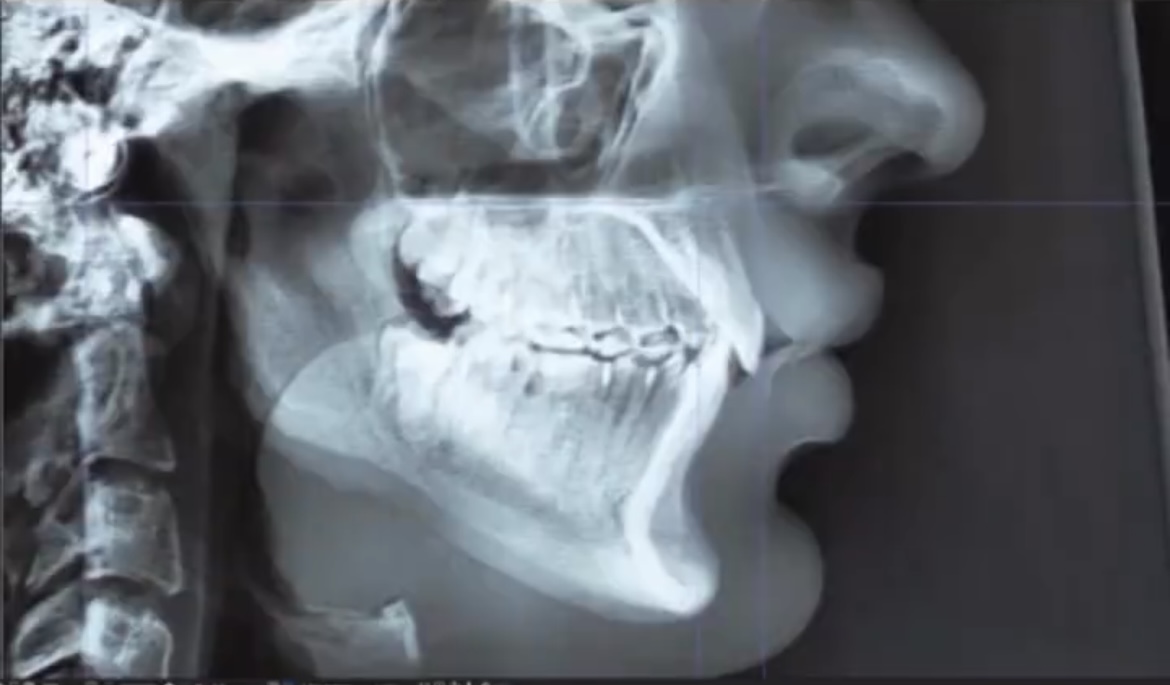

Look at the xrays. Only thing that changed is that his dogshit hyoid bone was raised from mewing. Not really anything aside from that. Mandible and maxilla are in the exact same positions. Look at his adam's apple and submental. Probably mouth breathed his entire life with extremely weak muscles that couldn't even hold his hyoid up. He even said he couldn't eat food without swallowing it with water lmfao. Mewing simply made his hyoid look more like a young man's and not a geriatric man's. Sucking dick and swallowing can accomplish the same for all the mew copers on here.

Call me low iq but the x ray looks the exact same idk what this proof is

Just look at 20:00 and alternate between the two pictures, look at the bottom line especially where his lip area is.

His maxilla is more upswung, and his mandible is more forward as a result of it.

If you scale and line up the xrays properly, you would see the same thing.

Keep coping with those shitty pictures. You literally have a copy pasted xray with no change whatsoever, even slight.

look at the chin it litterly got forward